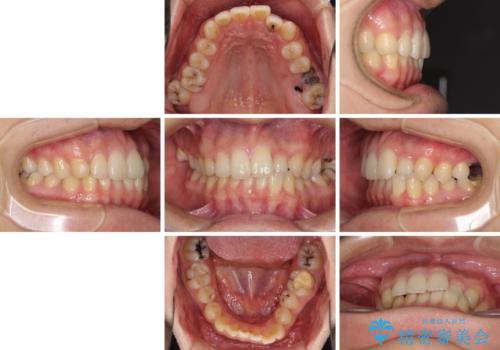

- 前歯のクロスバイトと、大学生のころから放置している虫歯を気にして来院された患者様です。

マウスピースでの矯正治療を希望されていましたが、前歯のクロスバイトは不十分な仕上がりや歯髄壊死などのリスクが高くなるため、術前にワイヤーで大まかに整えてからインビザラインにて矯正治療を行うこととしました。

奥歯の虫歯は抜歯が必要であったので、矯正治療前に抜歯をし、矯正治療と並行してインプラントによる補綴治療を行うこととしました。